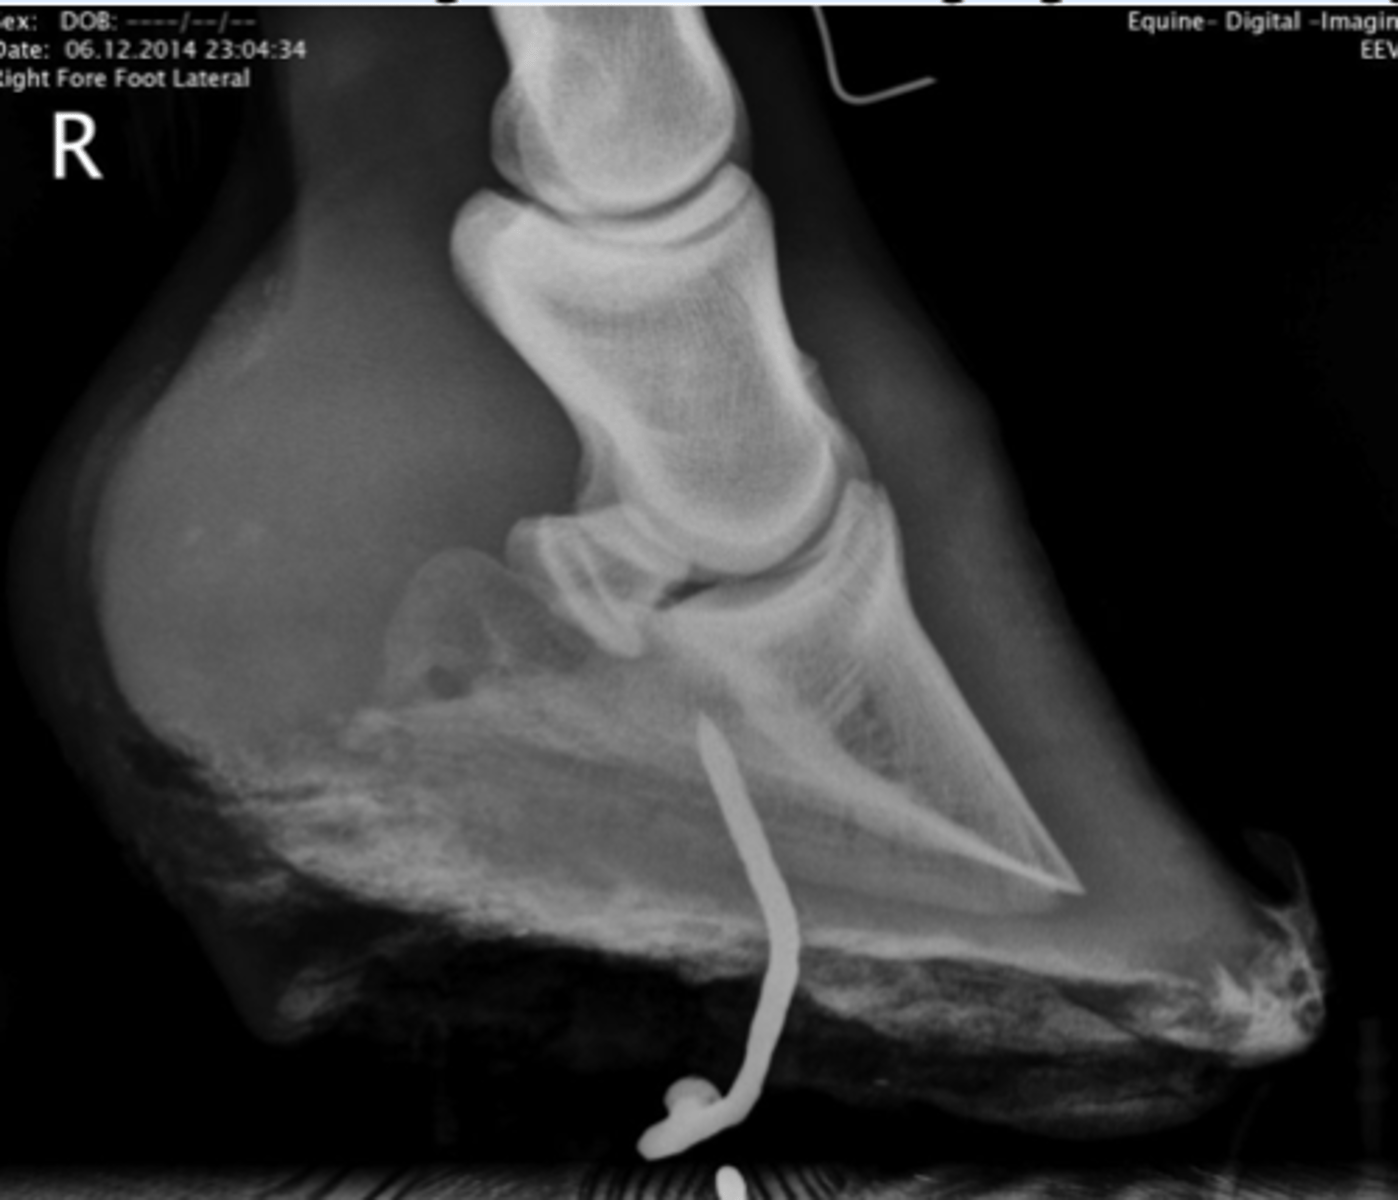

Røntgenbilleder af hasen

Hesten på billedet har haft et sår, der ikke har villet hele gennem 6 måneder. Hvad er det mest relevante diagnostiske tiltag for denne patient?

- Tryktest af talocruralleddet

- Svaberprøve til bakteriologisk undersøgelse af såret

- Røntgenbilleder af hasen

- Bøjeprøver